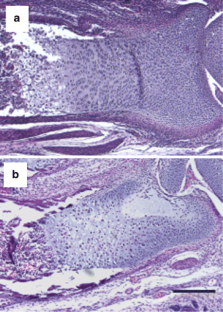

Fig. 3